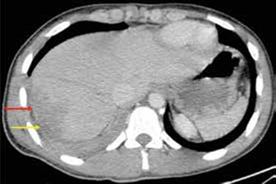

En este mismo grupo de 14 pacientes operados, 12 tuvieron lesiones que requerían manejo quirúrgico; en dos (el 4 y el 8), la laparotomía no fue terapéutica (figuras 4 y 5); en tres, el abdomen no se pudo evaluar, aunque había estabilidad hemodinámica, por lo cual se les practicó TC; el número 1 tenía politrauma, llegó intubado y sedado a la institución, al igual que el número 12; el número 2 tenía trauma raquimedular asociado.

En 48 de los 62 pacientes se optó por un manejo no operatorio por los hallazgos de la TC. En dos de ellos, sometidos a cirugía temprana por criterio del cirujano, la laparotomía fue terapéutica: en uno, hubo trauma grado II en espejo en el intestino delgado que debió ser corregido y, en el otro, trauma grado II de recto intraperitoneal que debió ser corregido y se acompañó de colostomía. En este último paciente el protocolo de la TC fue incompleto por ausencia de medio de contraste rectal. Estos dos pacientes no presentaron complicaciones posquirúrgicas.

En este mismo grupo de 48 pacientes sin indicación quirúrgica inicial, otros tres debieron intervenirse quirúrgicamente después de un tiempo de observación clínica por presentar dolor no controlado. Dos de ellos presentaban heridas toracoabdominales derechas; en uno, los hallazgos quirúrgicos fueron trauma hepático de grado II, hemoperitoneo de 300 ml y lesión del hemidiafragma derecho y, en el otro, lesión del hemidiafragma derecho y trauma hepático de grado II, por lo cual sus intervenciones se consideran no terapéuticas (verdaderos negativos, figuras 6 y 7). El tercer paciente no presentaba lesiones viscerales. Ninguno de los tres sufrió complicaciones posquirúrgicas. Los restantes 43 pacientes fueron dados de alta sin complicaciones después del tratamiento no operatorio.